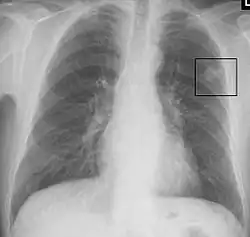

![]() Przekrój przez płuca. Biały fragment w górnym płacie to rak. Czarne zabarwienia w pozostałych miejscach wskazują, że pacjent był palaczem. | |